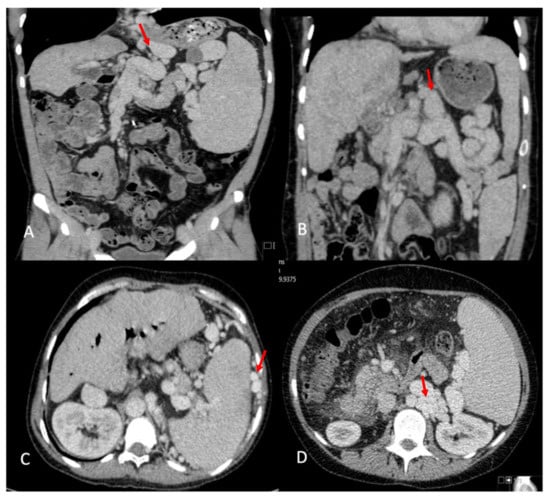

In total, 24 (72.7%) patients were found to have significant intra-abdominal variceal collaterals distributed in different territories (Figure 2A–D); retroperitoneal varices were most frequently observed (22 cases; 64.7%), followed by perisplenic (41.2%), lienorenal (26.5%), and left gastric territory (seven cases; 20.6%) (Table 3). These shunts appear to contribute to abnormalities observed in the portal vein (PV), as detected on imaging. On CT, 16 (47%) patients had an attenuated PV, of whom 14 (87.5%) had SPSS compared to 7 (39.9%) of 18 (53%) patients with a normal PV appearance on CT. The shunts in patients with attenuated PV tended to have more territories involved, with a median of two territories (1–4) compared to one (1–3) in the normal PV group, but this was not statistically different. On the USs, 14 patients (41.7%) either had absent flow (five), reversed flow (five), or low-velocity antegrade flow (two), of which 11 (78.5%) had attenuated PV on CT. Portal vein thrombosis (PVT) was found in one patient at transplant and was managed with eversion thrombectomy. This patient had an attenuated PV on CT and reversed flow on their US. In six patients, the PV was reported as small in the operating notes, one patient required an inter-positional graft, and another had a low anastomosis after resecting the narrowed extrahepatic PV segment.

Figure 2.

Visceral portosystemic shunts on imaging. (A) Left gastric vein varix. (B) Lieno-renal shunt. (C) Perisplenic varices. (D) Retroperitoneal varices.